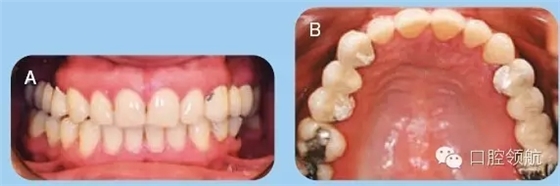

35歲白人女性患者,前來牙周科咨詢,要求修復(fù)兩側(cè)上頜象限的無牙頜區(qū)域。已存的固定橋修復(fù)失敗,患者要求行種植修復(fù)缺失牙。拆除患者已存的固定橋,重新預(yù)備基牙,并粘結(jié)臨時(shí)橋(圖1)。

圖1 (A)上頜以及下頜牙咬合關(guān)系的口內(nèi)照。(B)上頜牙弓的牙合面觀。

● 兩側(cè)上頜1/4象限的缺牙區(qū)牙槽嵴在頰舌向以及垂直向形態(tài)欠佳(Seibert III類)(圖1)。